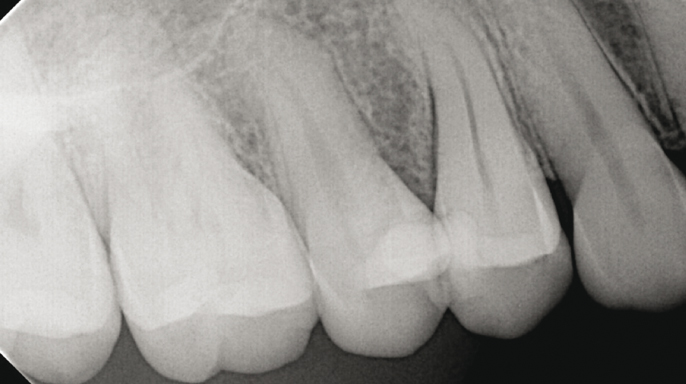

Interview / reportážVyžadují všechny prasklé zuby ošetření kořenových kanálků? Jak brzy po endodontickém ošetření by měl prasklý zub dostat korunkovou rekonstrukci? Jak lze předpovědět prognózu prasklého zubu? To jsou otázky, které často slýchám od přátel i kolegů.

EndodonciePacient se dostavil do ordinace, nespokojený s estetickým výsledkem korunek na zubech 24 a 25. Klinické vyšetření prokázalo nevyhovující marginální uzávěr u obou korunek, a proto bylo indikováno zhotovení nových protetických rekonstrukcí.

Termín chirurgická endodoncie označuje obor stomatologie, který se zabývá diagnostikou a léčbou lézí endodontického původu, jež nedostatečně reagují na konvenční endodontické ošetření nebo je nelze konvenční cestou ošetřit vůbec.¹ Cílem chirurgické endodoncie je dosažení trojrozměrného vyčištění, opracování a zaplnění apikální části kořenového kanálkového systému, která není přístupná běžným ortográdním přístupem dřeňovou dutinou, ale pouze po odklopení chirurgického laloku (obr. 1.1).

Úspěšnost nechirurgického ošetření kořenových kanálků je vysoká; nicméně nedostatečné zaplnění a utěsnění anatomických složitostí zásadně ovlivňuje dlouhodobý úspěch endodontické léčby.